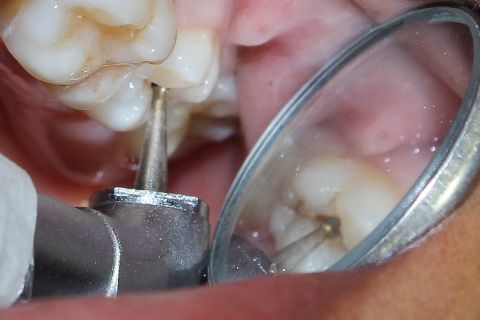

Remoção da lesão cariosa em esmalte com o uso de broca esférica dimantada nº1012

Curetagem de dentina amolecida

Uso da broca esférica carbide em baixa rotação para remoção de dentina cariada